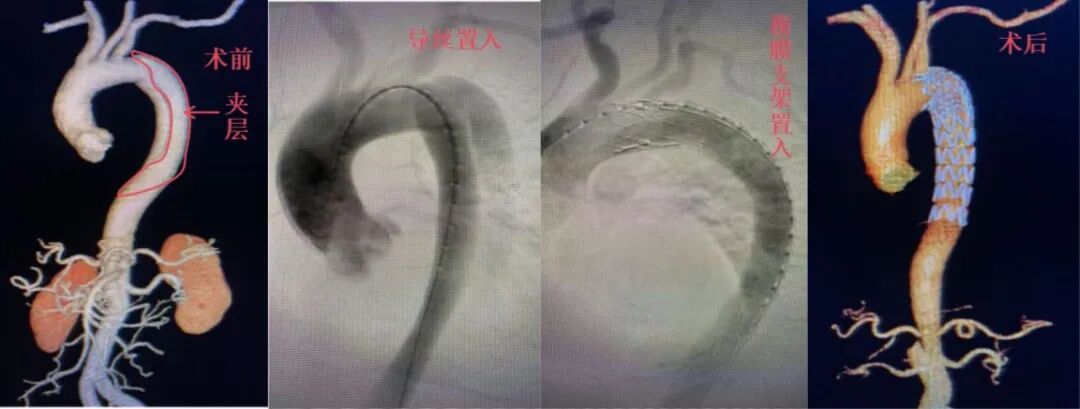

今年2月,一名52岁男性因剧烈腹痛辗转来院,血压达212/110mmHg,确诊DeBakey Ⅲ型主动脉夹层,夹层累及主动脉弓至双侧髂动脉,肠系膜血管、肾动脉均受累。介入科团队精准实施胸主动脉覆膜支架置入术,术后生命体征平稳。